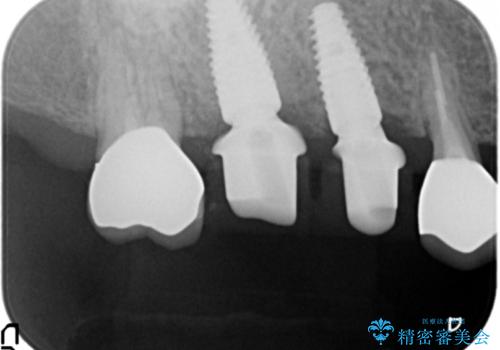

- 125.4万円(インプラント×2・チタンカスタムアバットメント×2・ジルコニアクラウン×4・仮歯×4)費用は治療当時の料金となります

インプラント治療が終了し、しっかりと咬合機能が回復しまた食事が楽しめるようになりました。